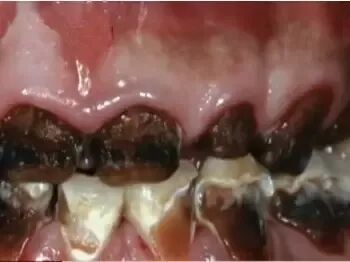

增加患龋齿风险——牙不美观

这副牙齿!!!虽然有点难以置信,但确实是真的牙齿,叫做“可乐牙”。众所周知,碳酸饮料是一种酸性的液体,在与牙齿接触时会腐蚀表层的牙釉质,会让牙齿变得越来越敏感,无法承受正常程度的冷热酸甜,长此以往就会把一口好牙变成了“可乐牙”!生活中,有人用喝剩下的可乐刷马桶、去水垢、去锈等,效果很好,就是因为可乐中所含有的磷酸对那些顽固的污垢具有瓦解作用。如果长期大量地喝含有磷酸的饮料,对牙齿真的也具腐蚀性的破坏作用。

怪不得小编以前喝碳酸饮料,每次喝完都觉得牙齿涩涩的,一点都不光滑,原来是牙釉质这层保护膜被饮料中的酸腐蚀啦!好可怕!